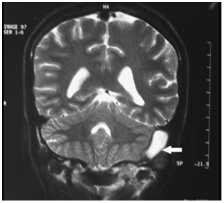

Although a CT scan is not required for patients with facial palsy, it can be useful in therapeutic planning. When cholesteatoma involves the Fallopian canal, it may also erode structures such as the labyrinth or tegmen. When petrous apicitis is suspected, a CT scan should be performed to make the diagnosis and to evaluate surrounding anatomy. CT scan will also aid in the diagnosis of intracranial complications that often accompany this condition.MRI accurately shows the site and extent of the apical abscess (Figure 4).

Figure 4 Axial T2 weighted MRI showing hyper intense region (arrow) in the left petrous apex.